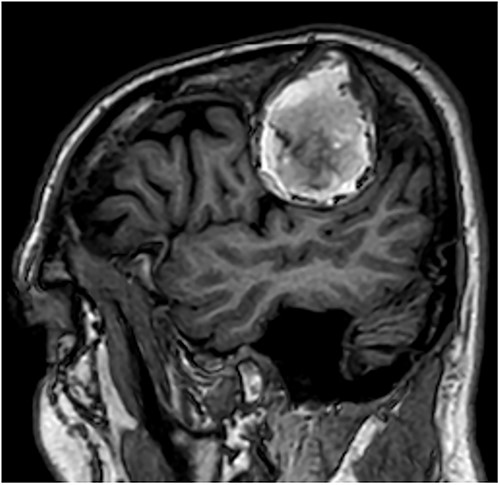

T1-weighted contrast-enhanced sagittal MRI scan showing the lesion with intralesional haemorrhagic products. There is no evidence of dural invasion.